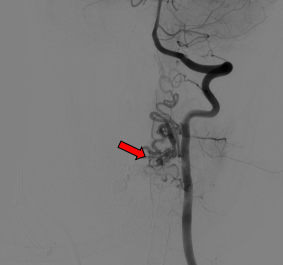

复合手术室行术中脊髓造影明确畸形血管团位置

手术当天,医疗团队首先在复合手术室内为患者进行了脊髓血管造影。在神经外科张昊副主任医师和邓敏峰博士的精准操作下,术中脊髓造影成功明确了畸形血管团的“位置”。

畸形血管团切除后立即脊髓造影明确完整切除

切除完成后,再次进行了造影复核,确认畸形血管团已被完全切除,手术取得了圆满成功。